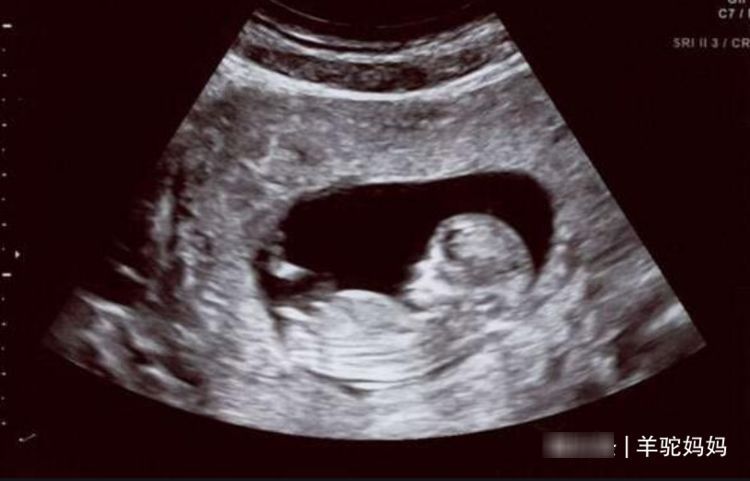

这些过程都是十分痛苦的,但是在孕期也有快乐的时候,比如看着日益变大的肚子,这种成就感真的是溢于言表,并且在每一次产检的时候都能和宝宝见到短暂的一面。

这更是会让新手父母兴奋不已,而且在孕期家里人对自己的呵护更是会感受得更加深刻,这都是整个孕期最快乐的瞬间,其实最值得让父母开心的还是每次产检医生说宝宝发育的很好的时候。

短短一句话真的是可以让你快乐好久,因为孕期宝妈最担心的就是孩子的健康,发育的是不是正常,所以对产检也是又恨又爱的感觉。

孕妈真的只有在产检之后才是真正将悬着的心放下来了,因为不产检期间是真的无法感知宝宝到底发育的好不好,产检之后给出结果宝妈才是真的能放心一点。